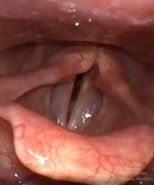

Клинический пример №6. Удаление полипа правой голосовой складки с использованием СО-2 лазера.

После операции воспалительные проявления со стороны голосовой складки едва заметны.

Рис 6Б Полип (ангиоматозный) правой голосовой складки. До операции.

Рис 6Б. Полип (ангиоматозный) правой голосовой складки. 1 день после операции.